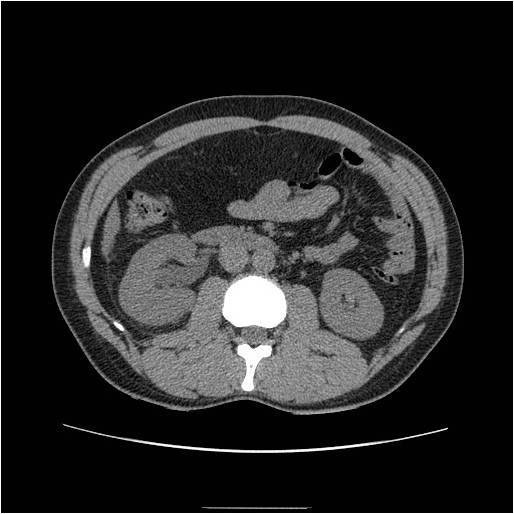

Scanner TDM sans injection à basse dose. Dilatation asymétrique des cavités pyélocalicielles rénales droites. Le scanner est maintenant utilisé de façon courante en urgence pour la prise en charge des patients avec une douleur du flanc. Cette stratégie s’est imposée par sa simplicité et sa rapidité, puisqu’elle remplace par un examen unique sans injection de produit de contraste les autres techniques (ASP, échographie et UIV) permettant une prise en charge rapide de ces patients